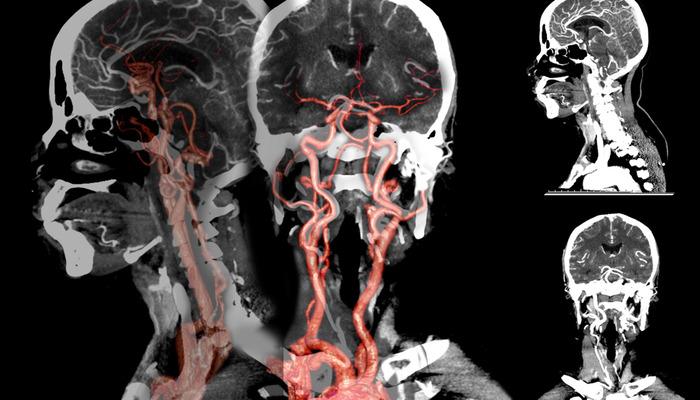

Doç. Dr., beyin kanamasının erkeklerde kadınlara göre daha sık görüldüğünü söyledi. Dr. Çakın, şunları söyledi: “Anevrizmal kanamalar, beyin atardamarlarındaki kabarcıklar nedeniyle meydana gelen beyin kanamaları olarak biliniyor. Özellikle sonbahar ve ilkbahar başlarında bu kanamaların yüzde 10 oranında arttığı gözlendi. Sigaranın etkisiyle beynin atardamarları tıkandı.”

Doç. Dr., beyin kanamasında genetik hastalıkların etkili olabileceğini söyledi. Hakan Çakın, “Yüksek tansiyon, sigara kullanımı ve ileri yaşa bağlı olarak oluşan bu kabarcıklar, mevsimsel döngülerde daha çabuk ortaya çıkıp beyin kanamalarına neden oluyor. Genetik anevrizmalara da daha sık rastlanıyor. Çocukluk döneminde, özellikle Japonya ve Finlandiya'da, ancak “bizim ülkemizde bu kadar yaygın değil. Belli bir yaştan sonra özellikle 30-50 yaş sonrasında hipertansiyon ve sigara kullanımının bu soruna etkisi büyüktür. At nalı böbrek hastalığı, diyaliz hastalarında ya da tansiyon sorunları ve genetik bozukluklar genç yaşta görülenlerde etkili olabiliyor” dedi.